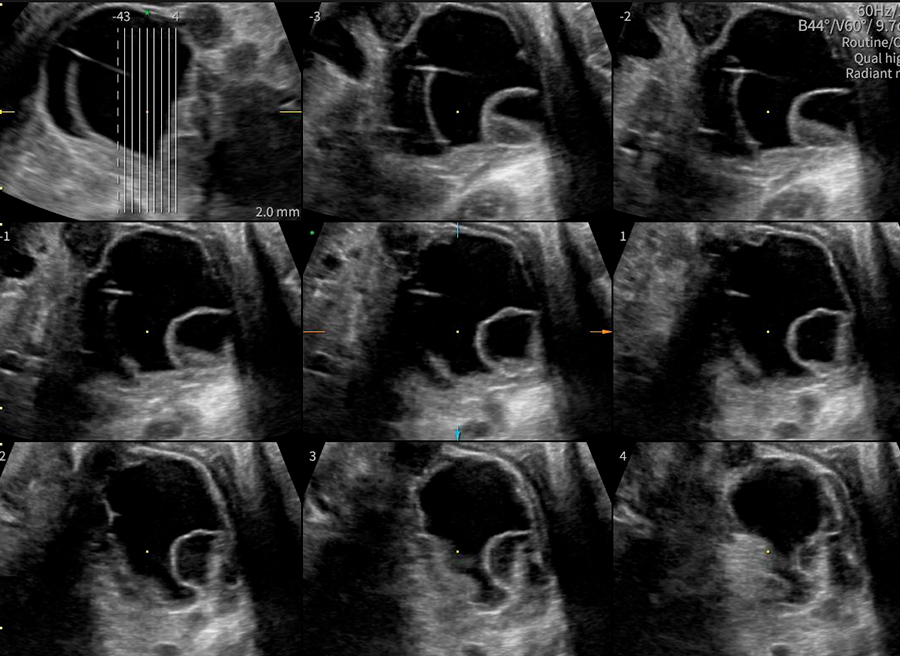

La ecografía ginecológica es un estudio por imágenes no invasivo que permite evaluar de forma precisa el útero, los ovarios y el sistema reproductor femenino. Es una herramienta fundamental para la detección temprana de alteraciones ginecológicas, el seguimiento de tratamientos y los controles preventivos.

En OBGYN Perú, realizamos ecografías ginecológicas con equipos de alta resolución, garantizando resultados confiables y una atención médica especializada.